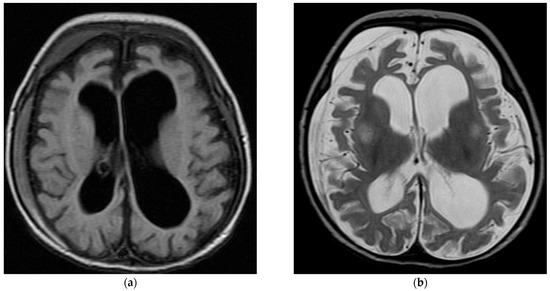

| Brain MRI | ||||

| Normal | 22 (48.9%) | 2 (25.0%) | 24 (45.3%) | 0.373 |

| Abnormal | 22 (48.9%) | 6 (75.0%) | 28 (52.8%) | |

| Positive MRI findings | ||||

| Generalized brain atrophy | 10 (45.5%) | 0 (0.0%) | 10 (35.7%) | 0.062 |

| Ventriculomegaly | 5 (22.7%) | 1 (16.7%) | 6 (21.4%) | >0.99 |

| Abnormal signal intensity | 6 (27.3%) | 0 (0.0%) | 6 (21.4%) | 0.289 |

| Thinning/dysgenesis of corpus callosum | 6 (27.3%) | 0 (0.0%) | 6 (21.4%) | 0.289 |

| Cerebellar atrophy | 2 (9.1%) | 1 (16.7%) | 3 (10.7%) | 0.530 |

| Lack of/delayed myelination | 1 (4.5%) | 1 (16.7%) | 2 (7.1%) | 0.389 |